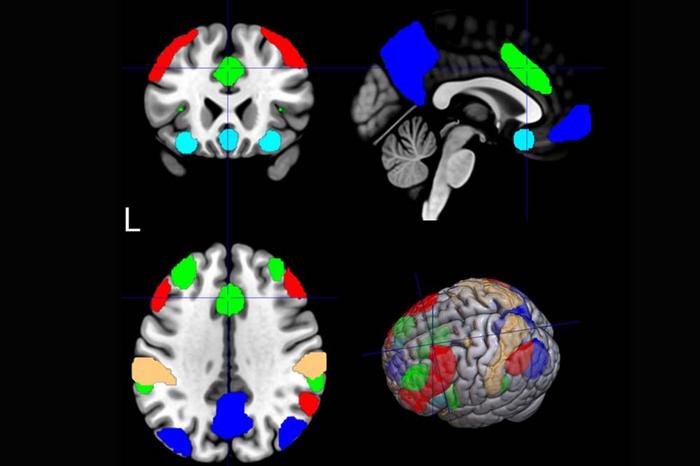

The Salience Network

Five large networks in the brain are highlighted. The salience network, which filters what is salient, or important to focus on, is green.

That analysis found that one neural network stood out: the salience network. It filters information to determine what’s salient, or important, to focus on. In the study, connectivity in the salience network was the best predictor of rTMS effectiveness.

“We were surprised to find that the salience network plays such a crucial role in smoking behavior. This makes the salience network a mechanistic bridge between rTMS neuromodulation and successful smoking cessation.”